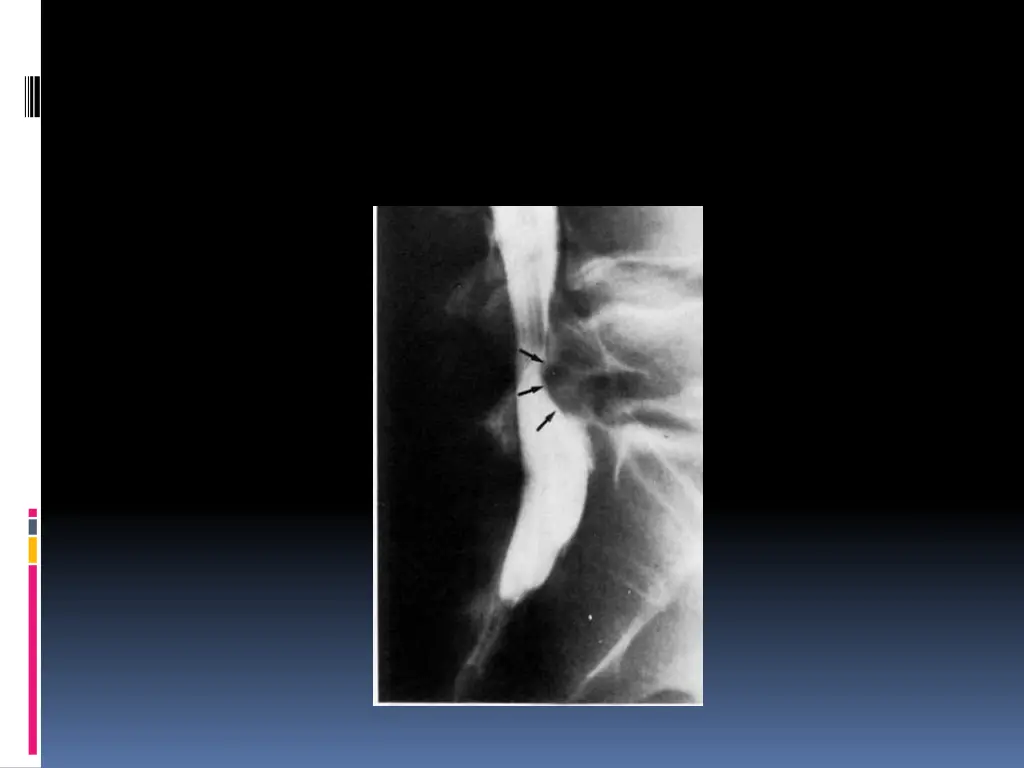

Examens complmentaires Interrogatoire + examen clinique=== diagnostic de sciatique commune Minimum : Un bilan inflammatoire Radiographies standards Incidences : -bassin de face debout (articulations sacro-iliaques,articulations coxo- f morales et du sacrum -rachis lombaire face + profil (statique, anomalie transitionnelle, qualit de l os,analyse des disques dont la hauteur peut tre diminu e, d veloppement arthrosique

SCANNER: Visualise la hernie, sa situation, son importance et la surface utile du canal rachidien. Coupes millim triques sus et sous-jacentes l espace discal v rifient l ventualit d une migration et son importance L IRM: Si la TDM ne d c le pas la hernie Si r cidive apr s CHX My lographie ou saccoradiculographie EMG